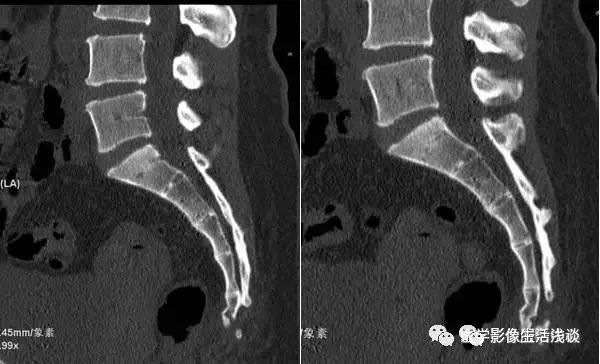

按不同的弯曲形态将其分为:均匀弯曲型、骶骨成角型、尾骨成角型、尾骨脱位型4种类型(见图1- 9),其中骶骨成角一般在S3、S4-5和S5部位,成角最大为70°。尾骨成角常在尾1-2或尾2-3部位,成角最大可达80°。

图1 均匀弯曲型;图2 骶骨成角型(骶3);图3 骶骨成角型(骶4-5);图4 骶骨成角型(骶5);图5尾骨成角型(尾1);图6 尾骨成角型(尾1-2);图7 尾骨成角型(尾2-3 );图8 尾骨脱位型;图9尾骨脱位型。